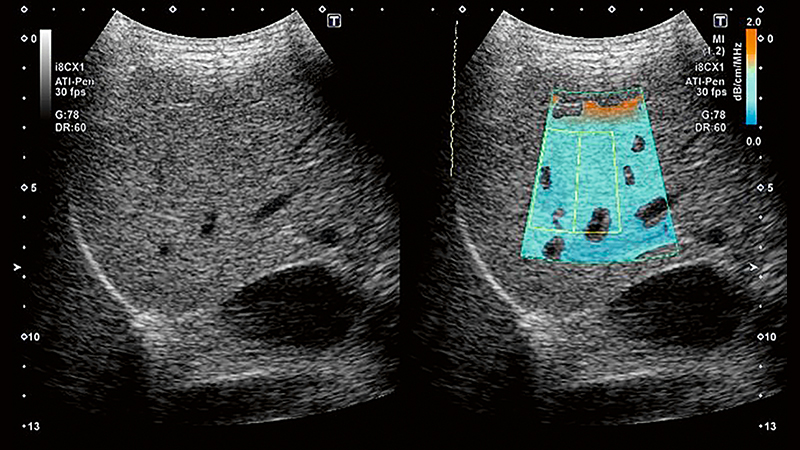

Візуалізація загасання (ATI) — це інноваційний інструмент, який може допомогти клініцистам в оцінці ступеня стеатозу. Рання характеристика наявного стеатозу є важливою як для надійного прогнозу, так і для ефективної терапії. ATI забезпечує кольорове кодування коефіцієнта загасання в тканинах печінки залежно від частоти.